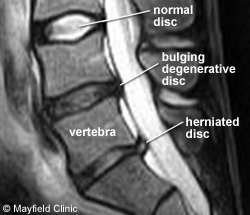

Ruptured Intervertebral Disc

This may be the most painful condition. A ruptured or herniated disc is one that bulges into the spinal canal, pressing on the nerve roots. This causes the nerve roots to become irritated. A ruptured disc may cause back pain and muscle spasms. More commonly it presents as sciatic pain. This is severe pain spreading down one leg and often into the foot.

Only a few people with lower back pain need a CT (computerized axial tomography) scan. A special machine takes an X-ray scan of the area. A computer turns this scan into a three-dimensional view of the back. This helps the doctor see if there is a ruptured disc that can’t be seen on regular X-rays. Other conditions that a CT scan can help detect are spinal stenosis,

tumors and infections of the spinal cord.

MRI

MRI (magnetic resonance imaging) is another way to make very clear pictures of parts of the spine. The MRI does not use X-rays or radioactive dyes. It can provide clearer pictures of soft tissues such as muscles, cartilage, ligaments, tendons and blood vessels, in addition to bone structure.